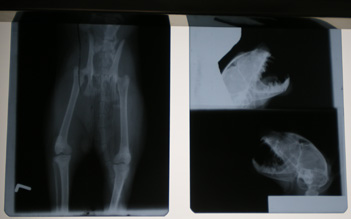

Radiološka dijagnostika sastavni je dio dijagnostičke ponude naše veterinarske ambulante. U radu se koristimo uređajem marke Philips MCD 105, koji je visoke frekvencije i minimalnog zračenja. Time je i osigurana optimalna zaštita od zračenja kako za pacijente, tako i za vlasnike ljubimaca.

Rendgenske slike su visoke kvalitete, a gotove su u svega nekoliko minuta nakon snimanja, zaslugom automatske razvijačice Protec COMPACT 35.

Rendgenološka pretraga neizostavna je dijagnostička metoda u slučajevima bolesti sustava za pokretanje pasa i mačaka, a također i drugih ljubimaca. Osim toga, izrazito je važna u dijagnozi bolesti srca i pluća kao i organa trbušne šupljine.